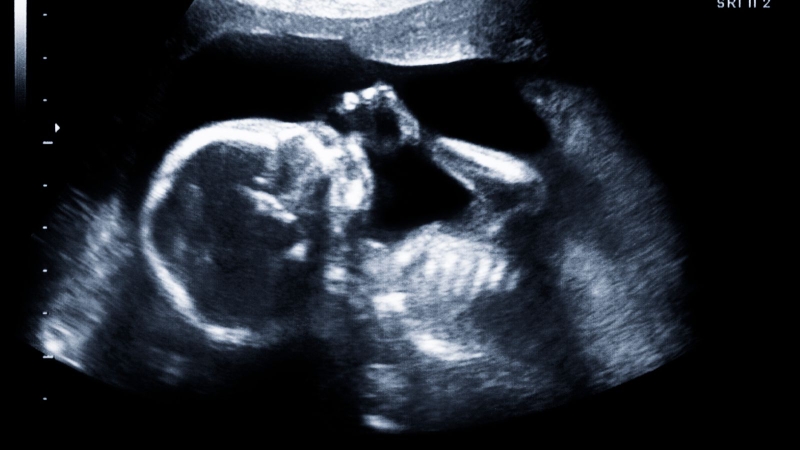

Độ dày bánh nhau thực chất là kích thước của nhau thai được đo lường thông qua hình ảnh siêu âm. Các bác sĩ thường xác định chỉ số này bằng cách đo khoảng cách vuông góc từ màng đệm đến thành tử cung tại vị trí có chiều dày lớn nhất. Điểm đo phổ biến và thường mang lại kết quả chuẩn xác nhất nằm ngay tại khu vực dây rốn cắm vào nhau thai.

Độ dày nhau thai là một chỉ số siêu âm giúp bác sĩ theo dõi sự phát triển của em bé trong bụng mẹ. Theo sinh lý bình thường, kích thước của bánh nhau sẽ tăng trưởng liên tục và tỷ lệ thuận với tuổi thai, trung bình cứ mỗi tuần trôi qua bánh nhau sẽ dày thêm khoảng 1 mm. Để mẹ bầu dễ hình dung, dưới đây là sự thay đổi kích thước tiêu chuẩn của bánh nhau tương ứng với từng giai đoạn thai kỳ: